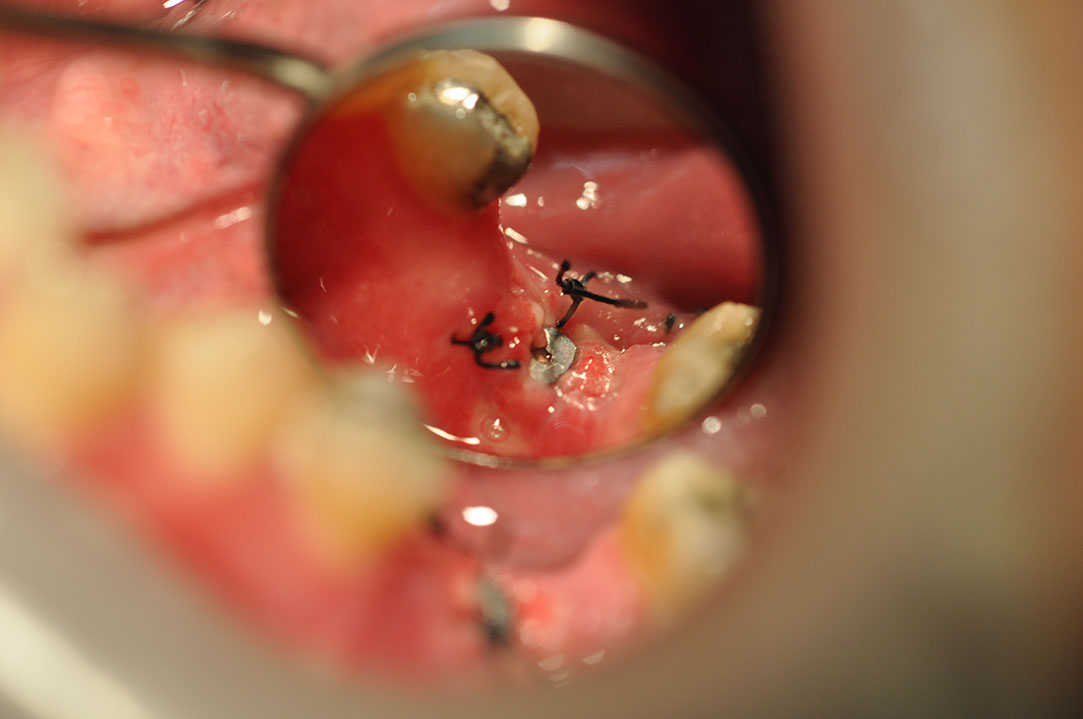

Implant 32La2.JPG

光牙醫